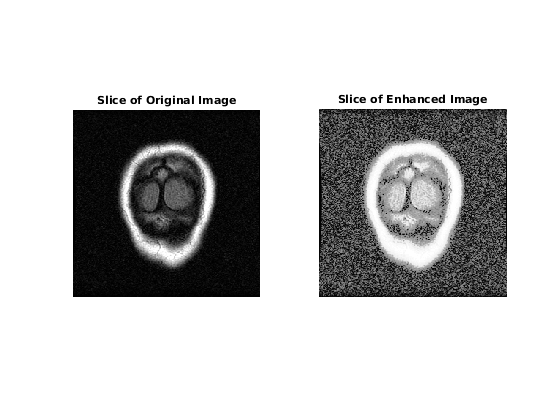

Отобразите первый срез данных для оригинального изображения и контрастного улучшенного изображения.

figure

subplot(1,2,1)

imshow(mristack(:,:,1))

title('Slice of Original Image')

subplot(1,2,2)

imshow(enhanced(:,:,1))

title('Slice of Enhanced Image')